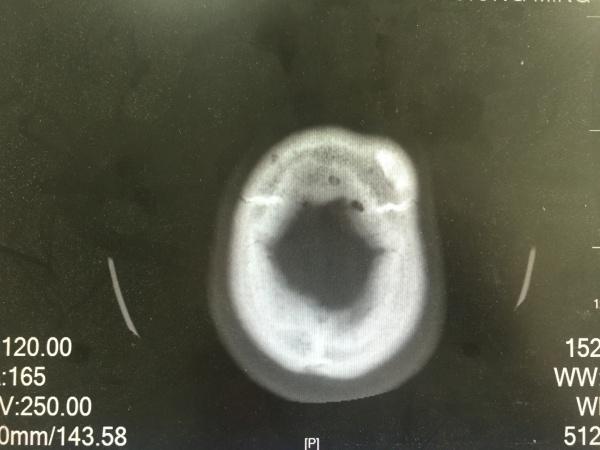

昨夜一位醉酒后外伤的病人,予以头颅CT检查发现的颅骨骨瘤,看着像在板障内,因患者醒酒后家属已送其回家,询问平素无明显不适,故无法跟踪及进一步明确。